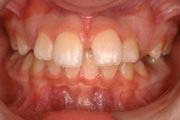

Crowding

Before